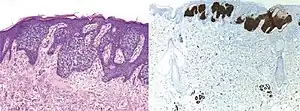

Comparison H&E stain (left) with BerEP4 immunohistochemistry staining (right) on a pathological section having BCC with squamous cell metaplasia. Only BCC cells are stained with BerEP4.[1]